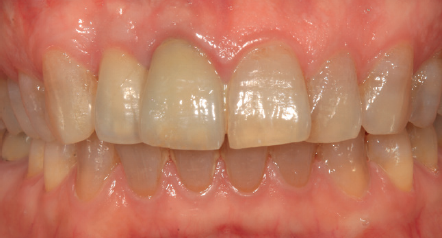

Tres meses después, se comienza con la fase protésica. El estado del tejido gingival es el correcto, aunque a nivel vestibular nos gustaría lograr un descenso del cenit del futuro diente, por lo que se planifica un injerto de conectivo que permita esta conformación de perfil de emergencia más adecuado. El caso se termina con coronas E max a nivel de 1.2 y 1.1, lográndose una sonrisa armónica y completa ente integrada en el resto de la sonrisa, en cuanto a color, emergencia y disposición de los márgenes gingivales (Figuras 14-15). La paciente continua en seguimien o durante años, mantenié dose la estabilidad de la rehabilitación llevada a cabo (Figura 16).